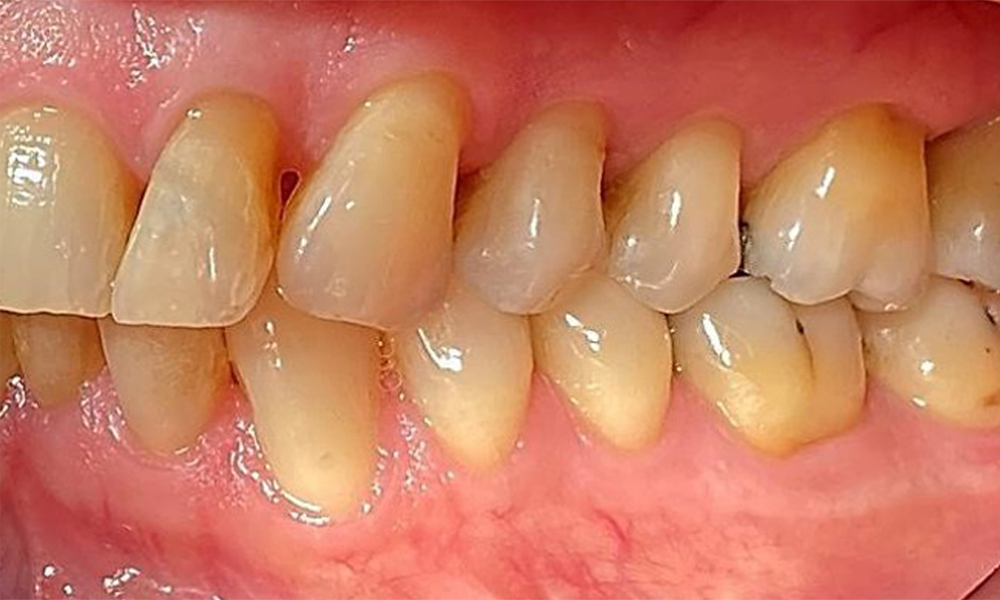

Der Patient hat ein vollbezahntes Gebiss mit 28 Zähnen, an welchen sich im Molaren- und Prämolarenbereich Amalgamfüllungen und Compositefüllungen befinden. An Zahn 14 zeigt sich ein sichtbarer klinischer Randspalt. Zahn 27 hat ein suffizientes Goldinlay. Zudem zeigen sich generalisierte Attritionen und Abrasionen. (Abb. 2, Abb. 3, Abb. 4, Abb. 5, Abb. 6)

Der Patient hat eine Parodontitis Stadium II, Grad B (5). Die klinischen Sondierungstiefen liegen mit 1-3mm im physiologischen Bereich. Lokalisierte Sondierungstiefen finden sich an 17 und 27 jeweils mesiopalatinal mit 5mm. Es liegen generalisierte Rezessionen von 1-3mm vor mit partiellem Verlust der Interdentalpapillen (Abb. 2, Abb. 3, Abb. 4)